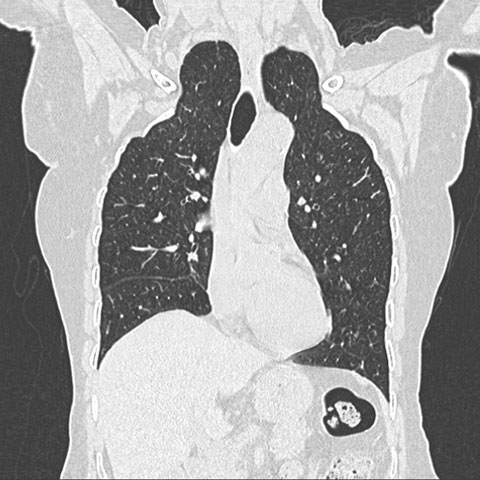

Apical lung hernia

Med J Aust 2007; 187 (6): 368. || doi: 10.5694/j.1326-5377.2007.tb01268.x

Acknowledgement: I thank Dr Bhavin Jankharia, Consultant Radiologist, JIC, Mumbai, India, for the computed tomography image.